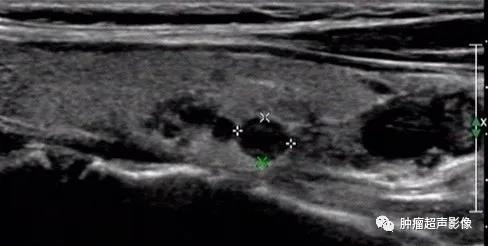

慢性肾脏疾病,血PTH升高,右侧2个(上图)、左侧1个(下图)增大的甲状旁腺腺体,呈边界清的低回声,与甲状腺分界清晰,部分形态不规则。